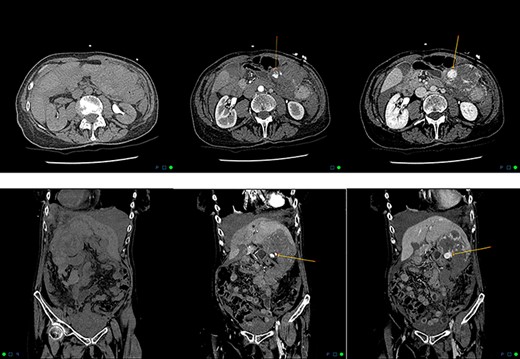

A 76-year-old woman presented with three syncopal episodes and a 2-day history of worsening abdominal pain. She had no nausea, vomiting, bowel changes or history of recent trauma. Apixaban (2.5 mg twice a day) was commenced 4 weeks prior for atrial fibrillation. Other past medical history included Parkinson’s disease. She had no history of malignancy or chronic liver disease. On presentation, she was pale, hypotensive (114/44 mmHg) and tachycardic (106 beats/minute). Physical examination demonstrated diffuse abdominal tenderness and distension without any signs of peritoneal irritation. Laboratory investigations revealed low haemoglobin (60 g/L), red blood cell count (2.35 × 1012/L) and haematocrit (0.215 L/L). Mean cell volume (92 fL) and platelets (190 × 109/L) were within range. Coagulation and liver function tests were unremarkable. Contrast-enhanced computerized tomography (CECT) reported a 62 × 83 × 90 mm heterogenous mass in the left lobe of the liver demonstrating contrast blush with large volume haemoperitoneum concerning for a bleeding hepatic neoplasm (Fig. 1). She was stabilized with five units of packed red blood cells before being transferred to our institute.

Axial and coronal reformats in non-contrast, arterial and delayed phases demonstrating contrast blush, with pooling within the left hepatic lobe haemangioma consistent with active bleeding.